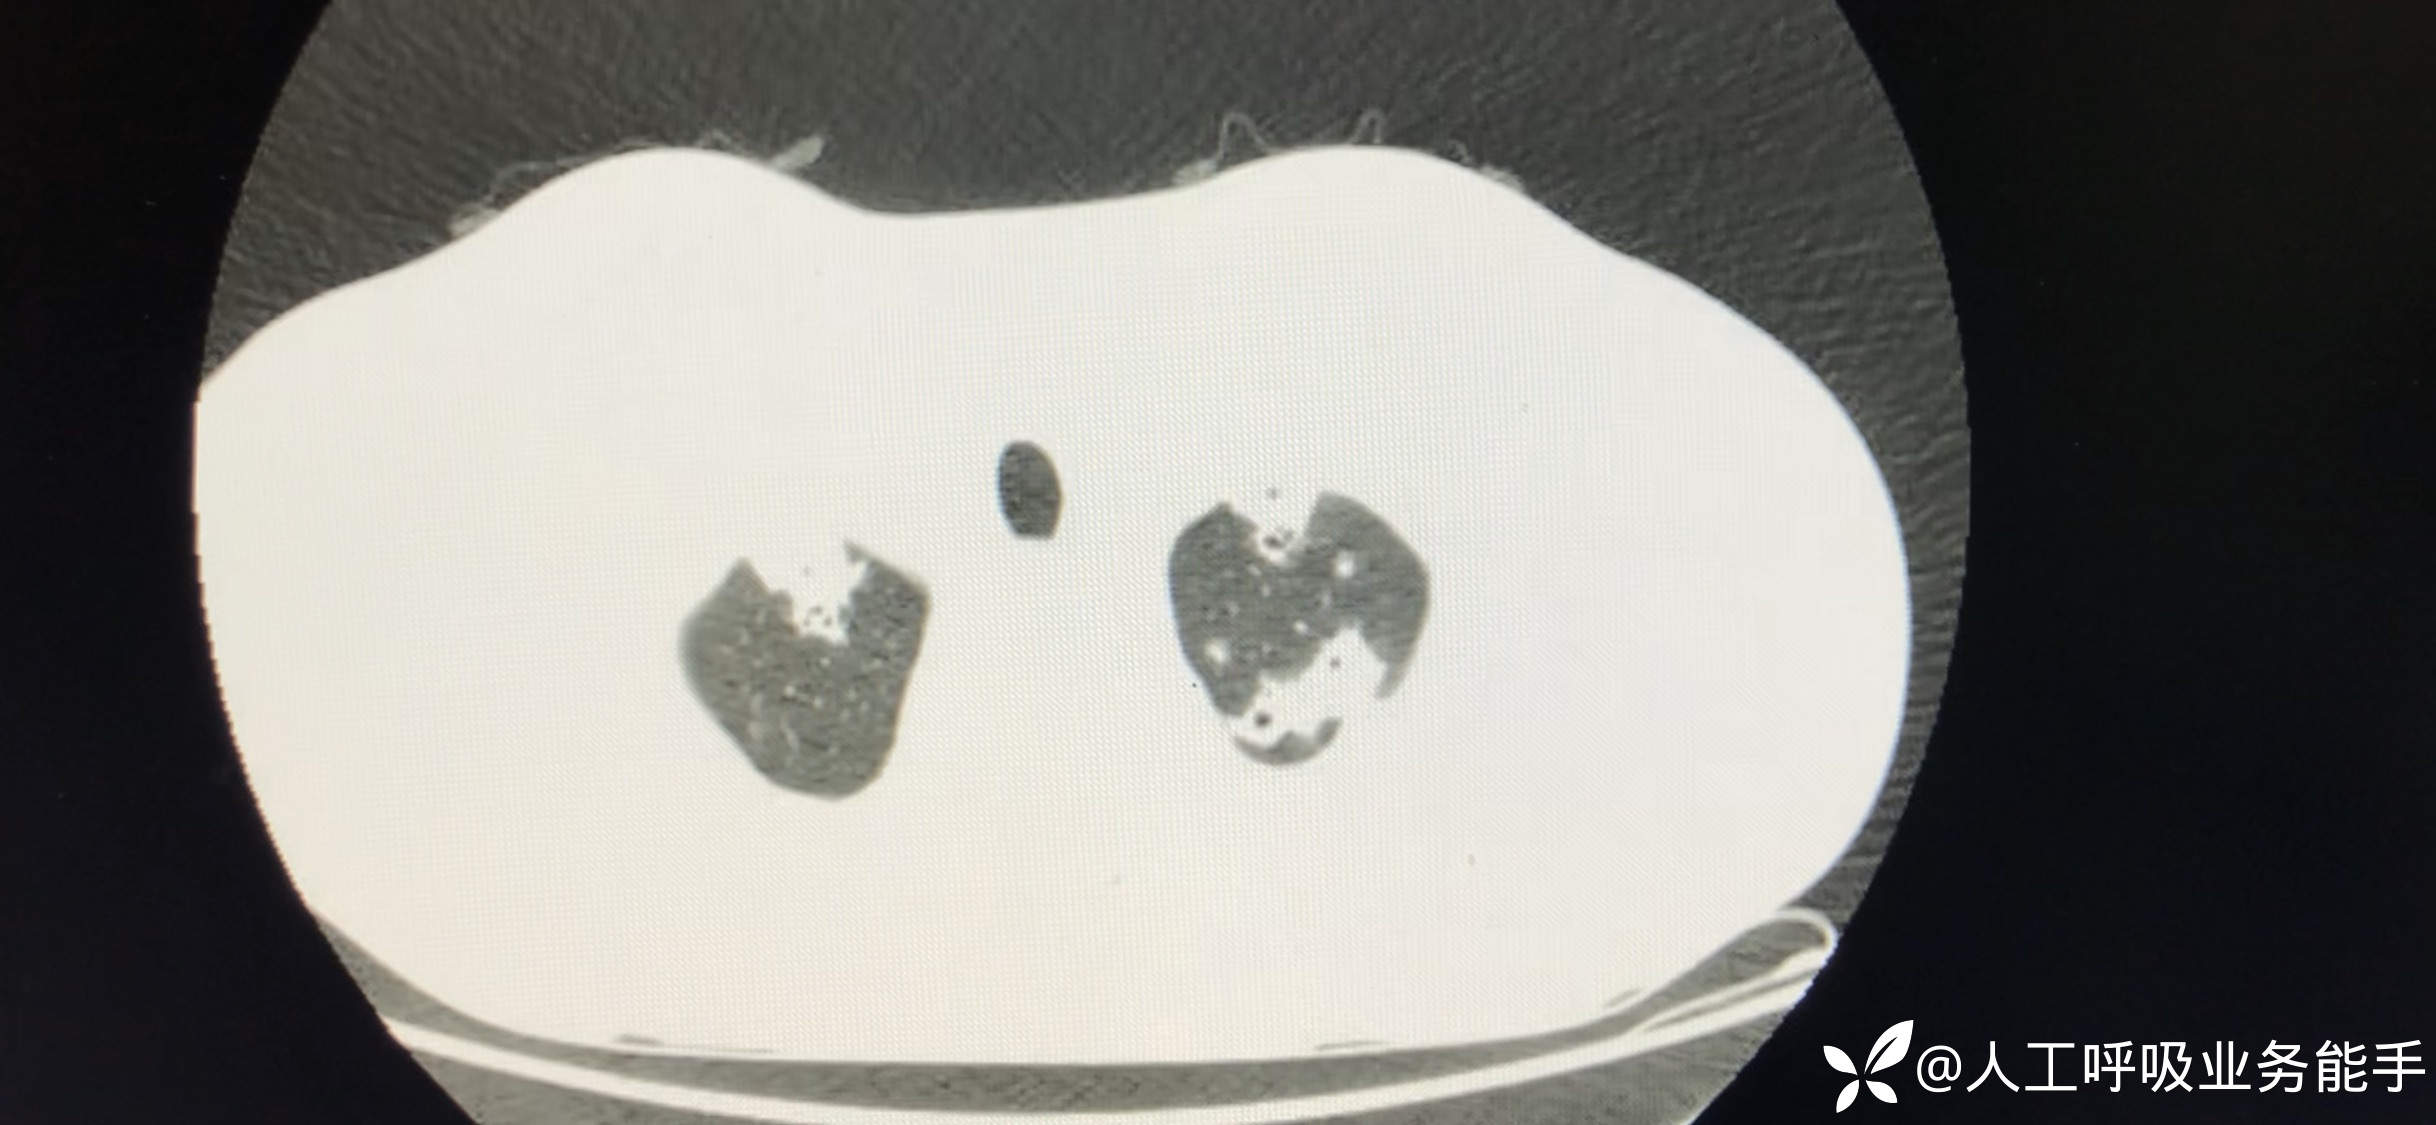

初诊影像: